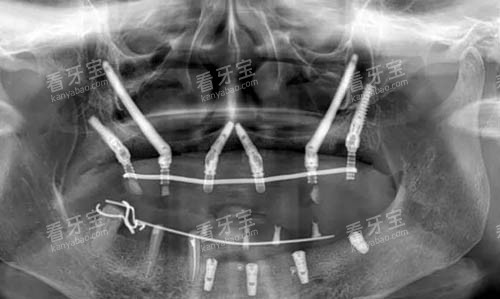

3.1 CT定位:术前规划的“数字导航”

(1)三维影像重建

术前需通过CBCT获取患者颌面部的三维数据,精度达0.1mm。医生可清晰观察到上颌窦形态、颧骨厚度、神经血管走向(如上颌神经管、眶下孔),避免术中损伤重要组织。

(3)智能化导板辅助

基于虚拟设计制作3D打印手术导板,确保术中种植体按预设位置更准一些植入。研究显示,使用导板的穿颧种植手术误差可控制在0.5mm以内,显著降低并发症风险(《中华口腔医学杂志》,2024)。

?每半年拍摄X线片,观察种植体周围骨密度变化;